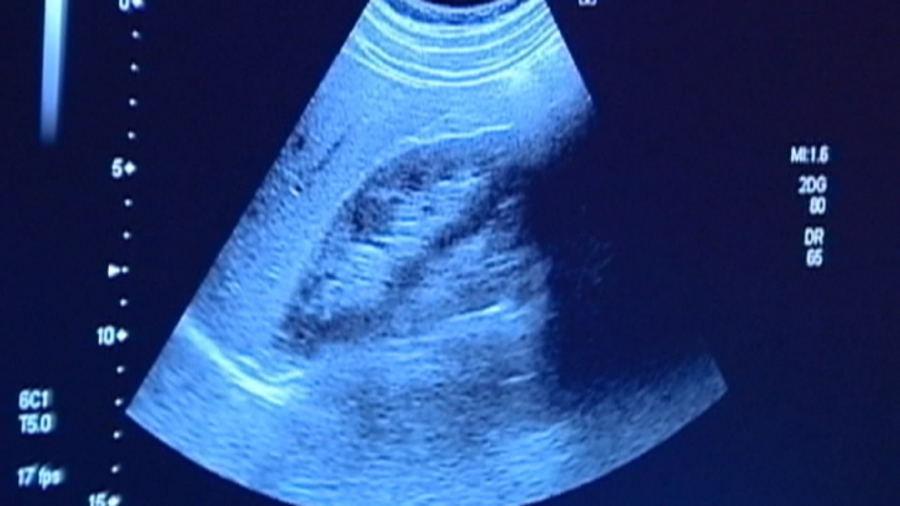

肝癌是台灣常見癌症,20多年來始終蟬聯癌症死亡率亞軍,有醫師警告,未來台灣肝癌的致病率原因,將從病毒性肝癌轉為脂肪肝,建議國人飲食力求均衡,避免接觸致癌食物,例如醃漬物或是油炸類高油食物。

炸得金黃酥脆的鹹酥雞,讓人一口接一口,炸雞排這類的高油食物,是不少民眾的最愛,只是一旦吃過量,很可能形成脂肪肝,成為肝癌的危險因子。根據統計,台灣每年有高達8千多人,死於肝癌和肝內膽管癌,而且台灣肝癌醫學會警告,未來台灣肝癌的致病率原因,將從過往的病毒性肝炎,轉為脂肪肝。